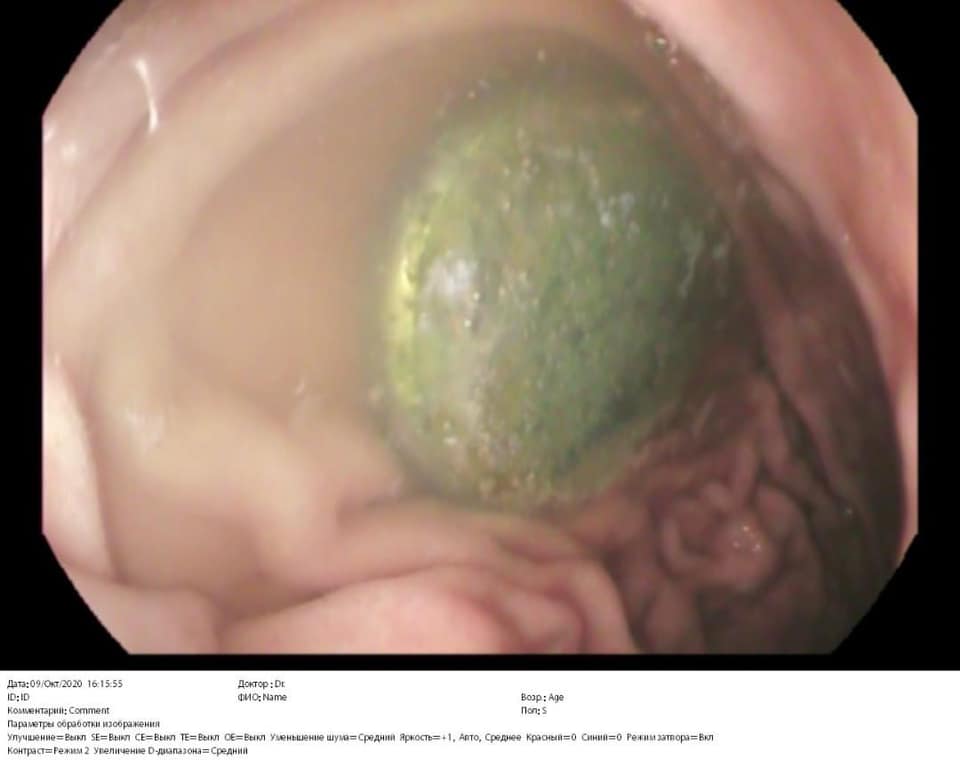

«Жінка вчасно встигла до нас приїхати і команда лікарів видалила нехитру забавку зі шлунка маленької. Діставали батарейку лікарка-ендоскопіст. Лікарі обійшлися без відкритої операції, за допомогою ендоскопа дістали стороннє тіло. Це не так просто зробити, адже лікарі працюють на відстані, батарейка слизька і зісковзує, доводиться робити кілька спроб її витягнути. Дівчинці пощастило, адже батарейка не встигла наробити біди», – зазначається у повідомленні.

“Дівчинку ми прооперували ендоскопічно під загальним наркозом. Батарейку встигли дістати зі шлунка, вона не встигла зашкодити маленькому шлунку”, – зазначила лікар-ендоскопіст ОХМАТДИТу Марта Лучак.